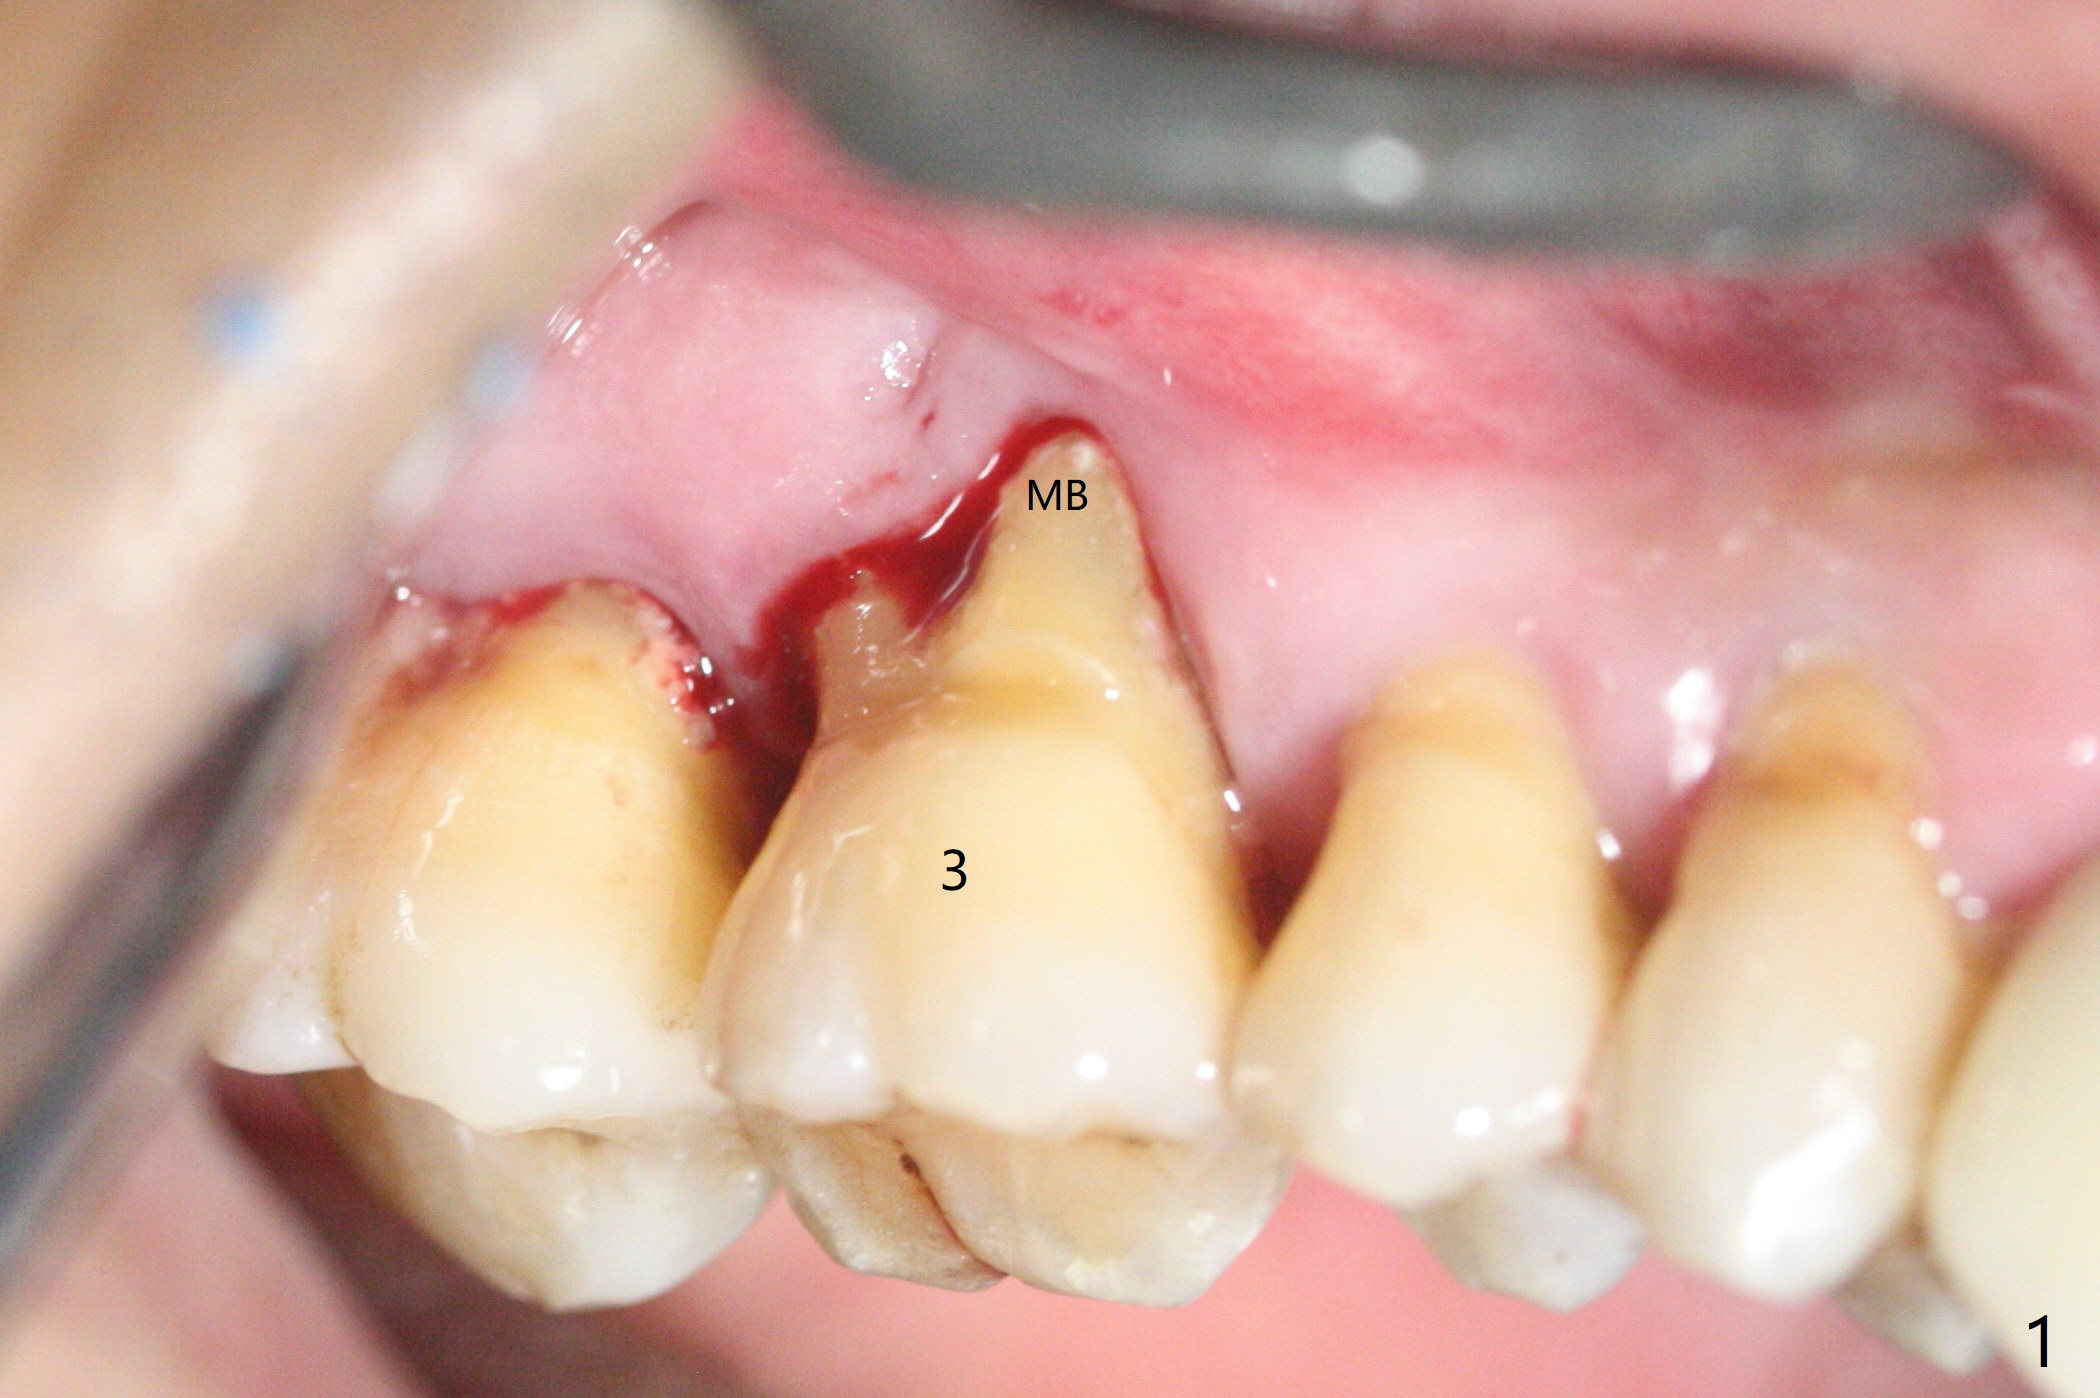

53岁男吸烟,牙周炎,咬合力大,3号牙颊侧(图一),腭侧(图二:P)牙龈退缩,尤其是近中颊侧根(图一:MB),拔牙后,中隔冠方(表面)有好像健康的牙龈(图三:*),近中,远中连接处切开(图三:虚线),将中隔牙龈推向近中颊侧牙槽窝(图四:箭头),修复退缩牙龈,而且暴露下面中隔(S),接着在它上面导板钻洞,避免软组织创伤。利用报废植体试图内提升(图五(红虚线:窦底)),最终正式植体完成提升(图六:黑*),初步在牙槽窝深部放置粘性骨粉(白*)后,放入基台,之后再次在植体,基台周围放置骨粉(图七:*),最后借助临时牙冠(图八,九:T)和外衬里(图八:R)封闭牙槽窝开口,G是近中颊侧迁移的牙龈。植体垂直进入上颌窦可以减少窦膜破裂(图五,六,九),术后没有鼻出血。术后1个月临时牙冠松动,去除牙冠和基台,安置愈合帽(图十)。表面骨粉遗失,但是颊侧移位的中隔牙龈好像帮助软组织预后。